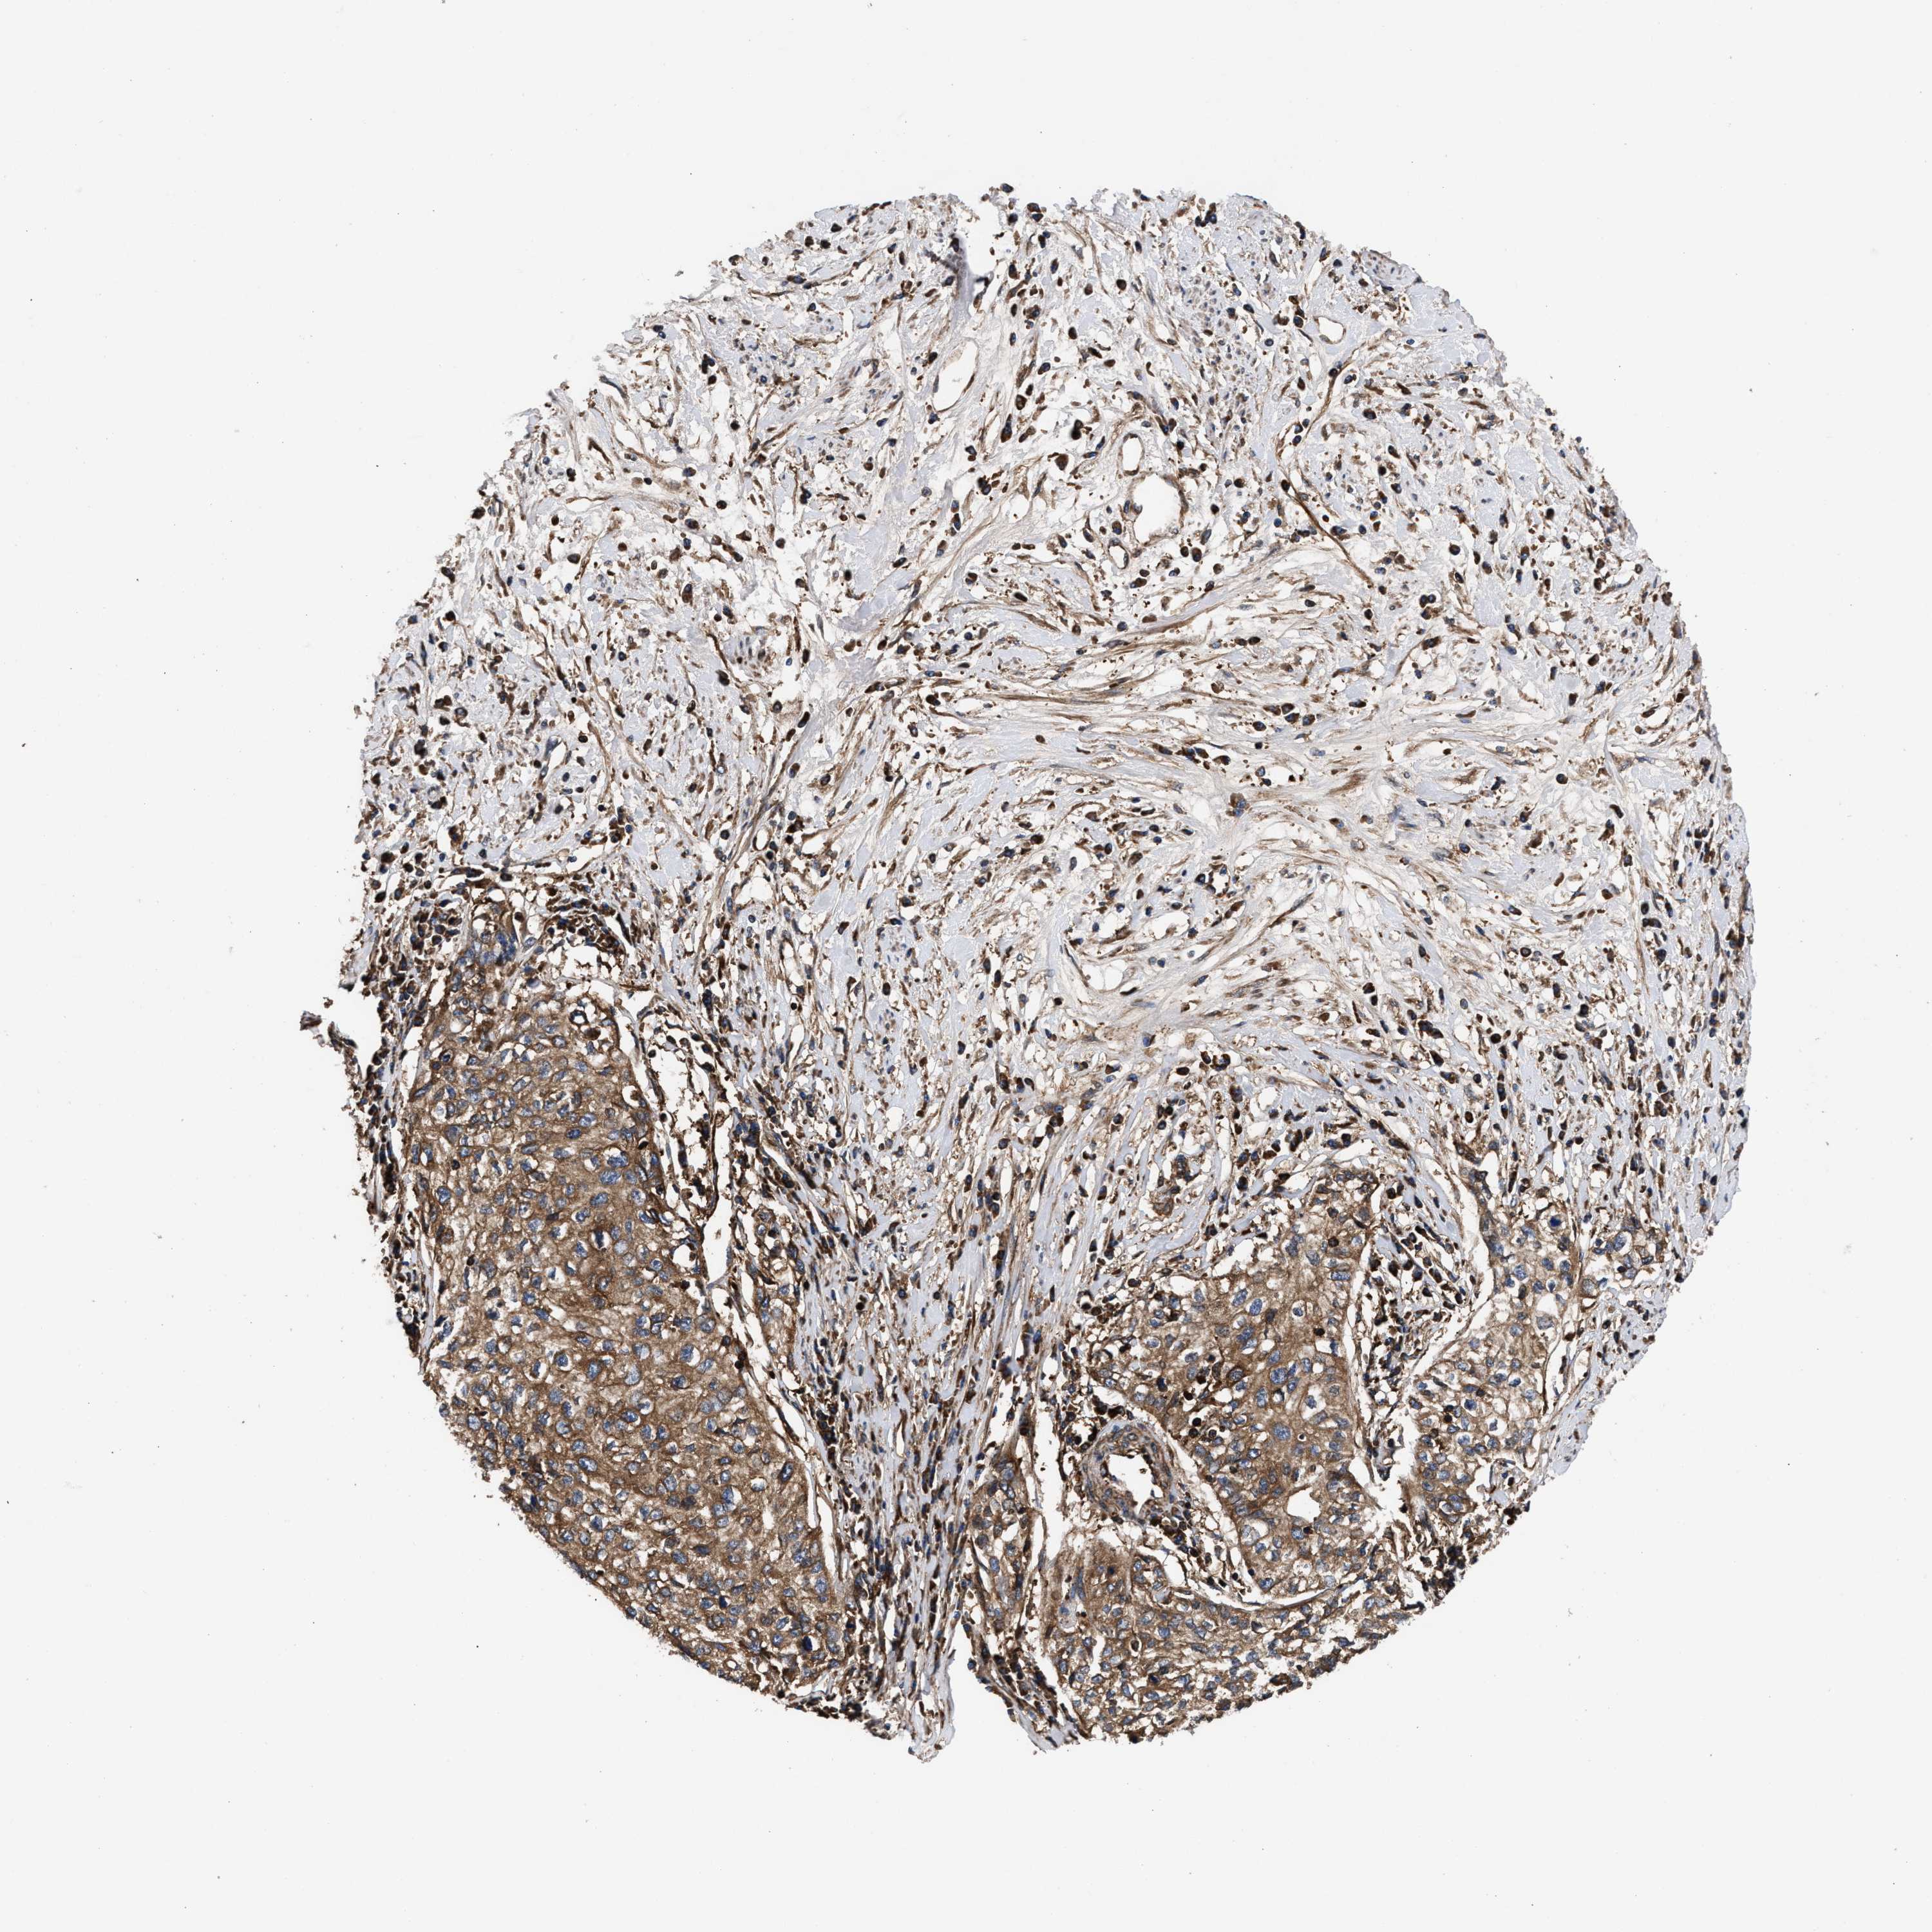

CERVICAL CANCER - Protein expressioni

A mouse-over function shows sample information and annotation data. Click on an image to view it in a full screen mode. Samples can be filtered based on level of antibody staining by selecting one or several of the following categories: high, medium, low and not detected. The assay and annotation is described here.

Note that samples used for immunohistochemistry by the Human Protein Atlas do not correspond to samples in the TCGA dataset.

Antibody stainingi

Antibody staining in the annotated cell types in the current human tissue is reported as not detected, low, medium, or high, based on conventional immunohistochemistry profiling in selected tissues. This score is based on the combination of the staining intensity and fraction of stained cells.

Each image is clickable and will lead to virtual microscopy that enables deeper exploration of all samples and also displays staining intensity scores, fraction scores and subcellular localization as well as patient and tissue information for each sample.

Antibody HPA021176

Antibody HPA021177

Antibody HPA027736

Squamous cell carcinoma, NOS

Adenocarcinoma, NOS